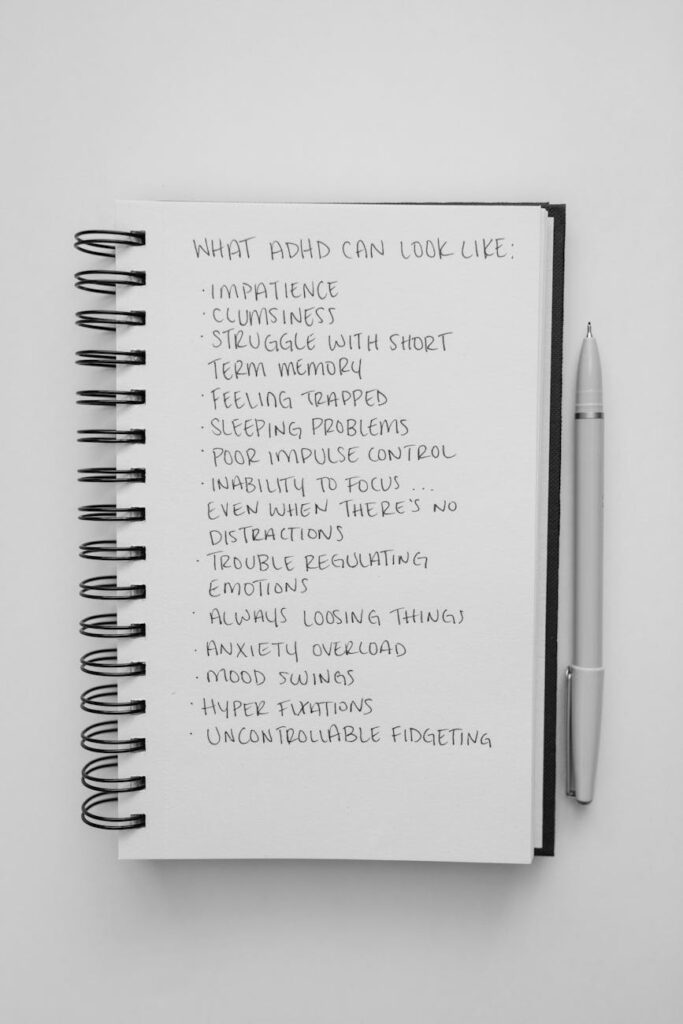

- Protocolo de Intervención para el Trastorno por Déficit de Atención e Hiperactividad (TDAH) en el AdultoI. Fundamentación Clínica El TDAH en adultos no es simplemente un déficit de atención, sino un trastorno de la autorregulación y las funciones ejecutivas. Según… Leer más: Protocolo de Intervención para el Trastorno por Déficit de Atención e Hiperactividad (TDAH) en el Adulto

- Protocolo para tratamiento de TDHA con AdultoIntroducción: Fundamentación Teórica del Abordaje El Trastorno por Déficit de Atención e Hiperactividad (TDAH) en adultos se manifiesta como un déficit persistente en la autorregulación… Leer más: Protocolo para tratamiento de TDHA con Adulto

- Esquema de Tratamiento Terapéutico: TDAH en el Adulto (12 Semanas)Este es un esquema de trabajo terapéutico integral para el abordaje del Trastorno por Déficit de Atención e Hiperactividad (TDAH) en adultos. Como psicólogo clínico,… Leer más: Esquema de Tratamiento Terapéutico: TDAH en el Adulto (12 Semanas)